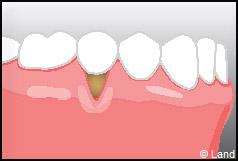

LES TECHNIQUES AVEC APPORT DE GENCIVE OU « GREFFE DE GENCIVE » :

Elles font appel à un prélèvement sur le patient à un endroit où elle est en excès, qui est ensuite posé sur la récession.

Il y a 2 types de « greffes » de gencives :